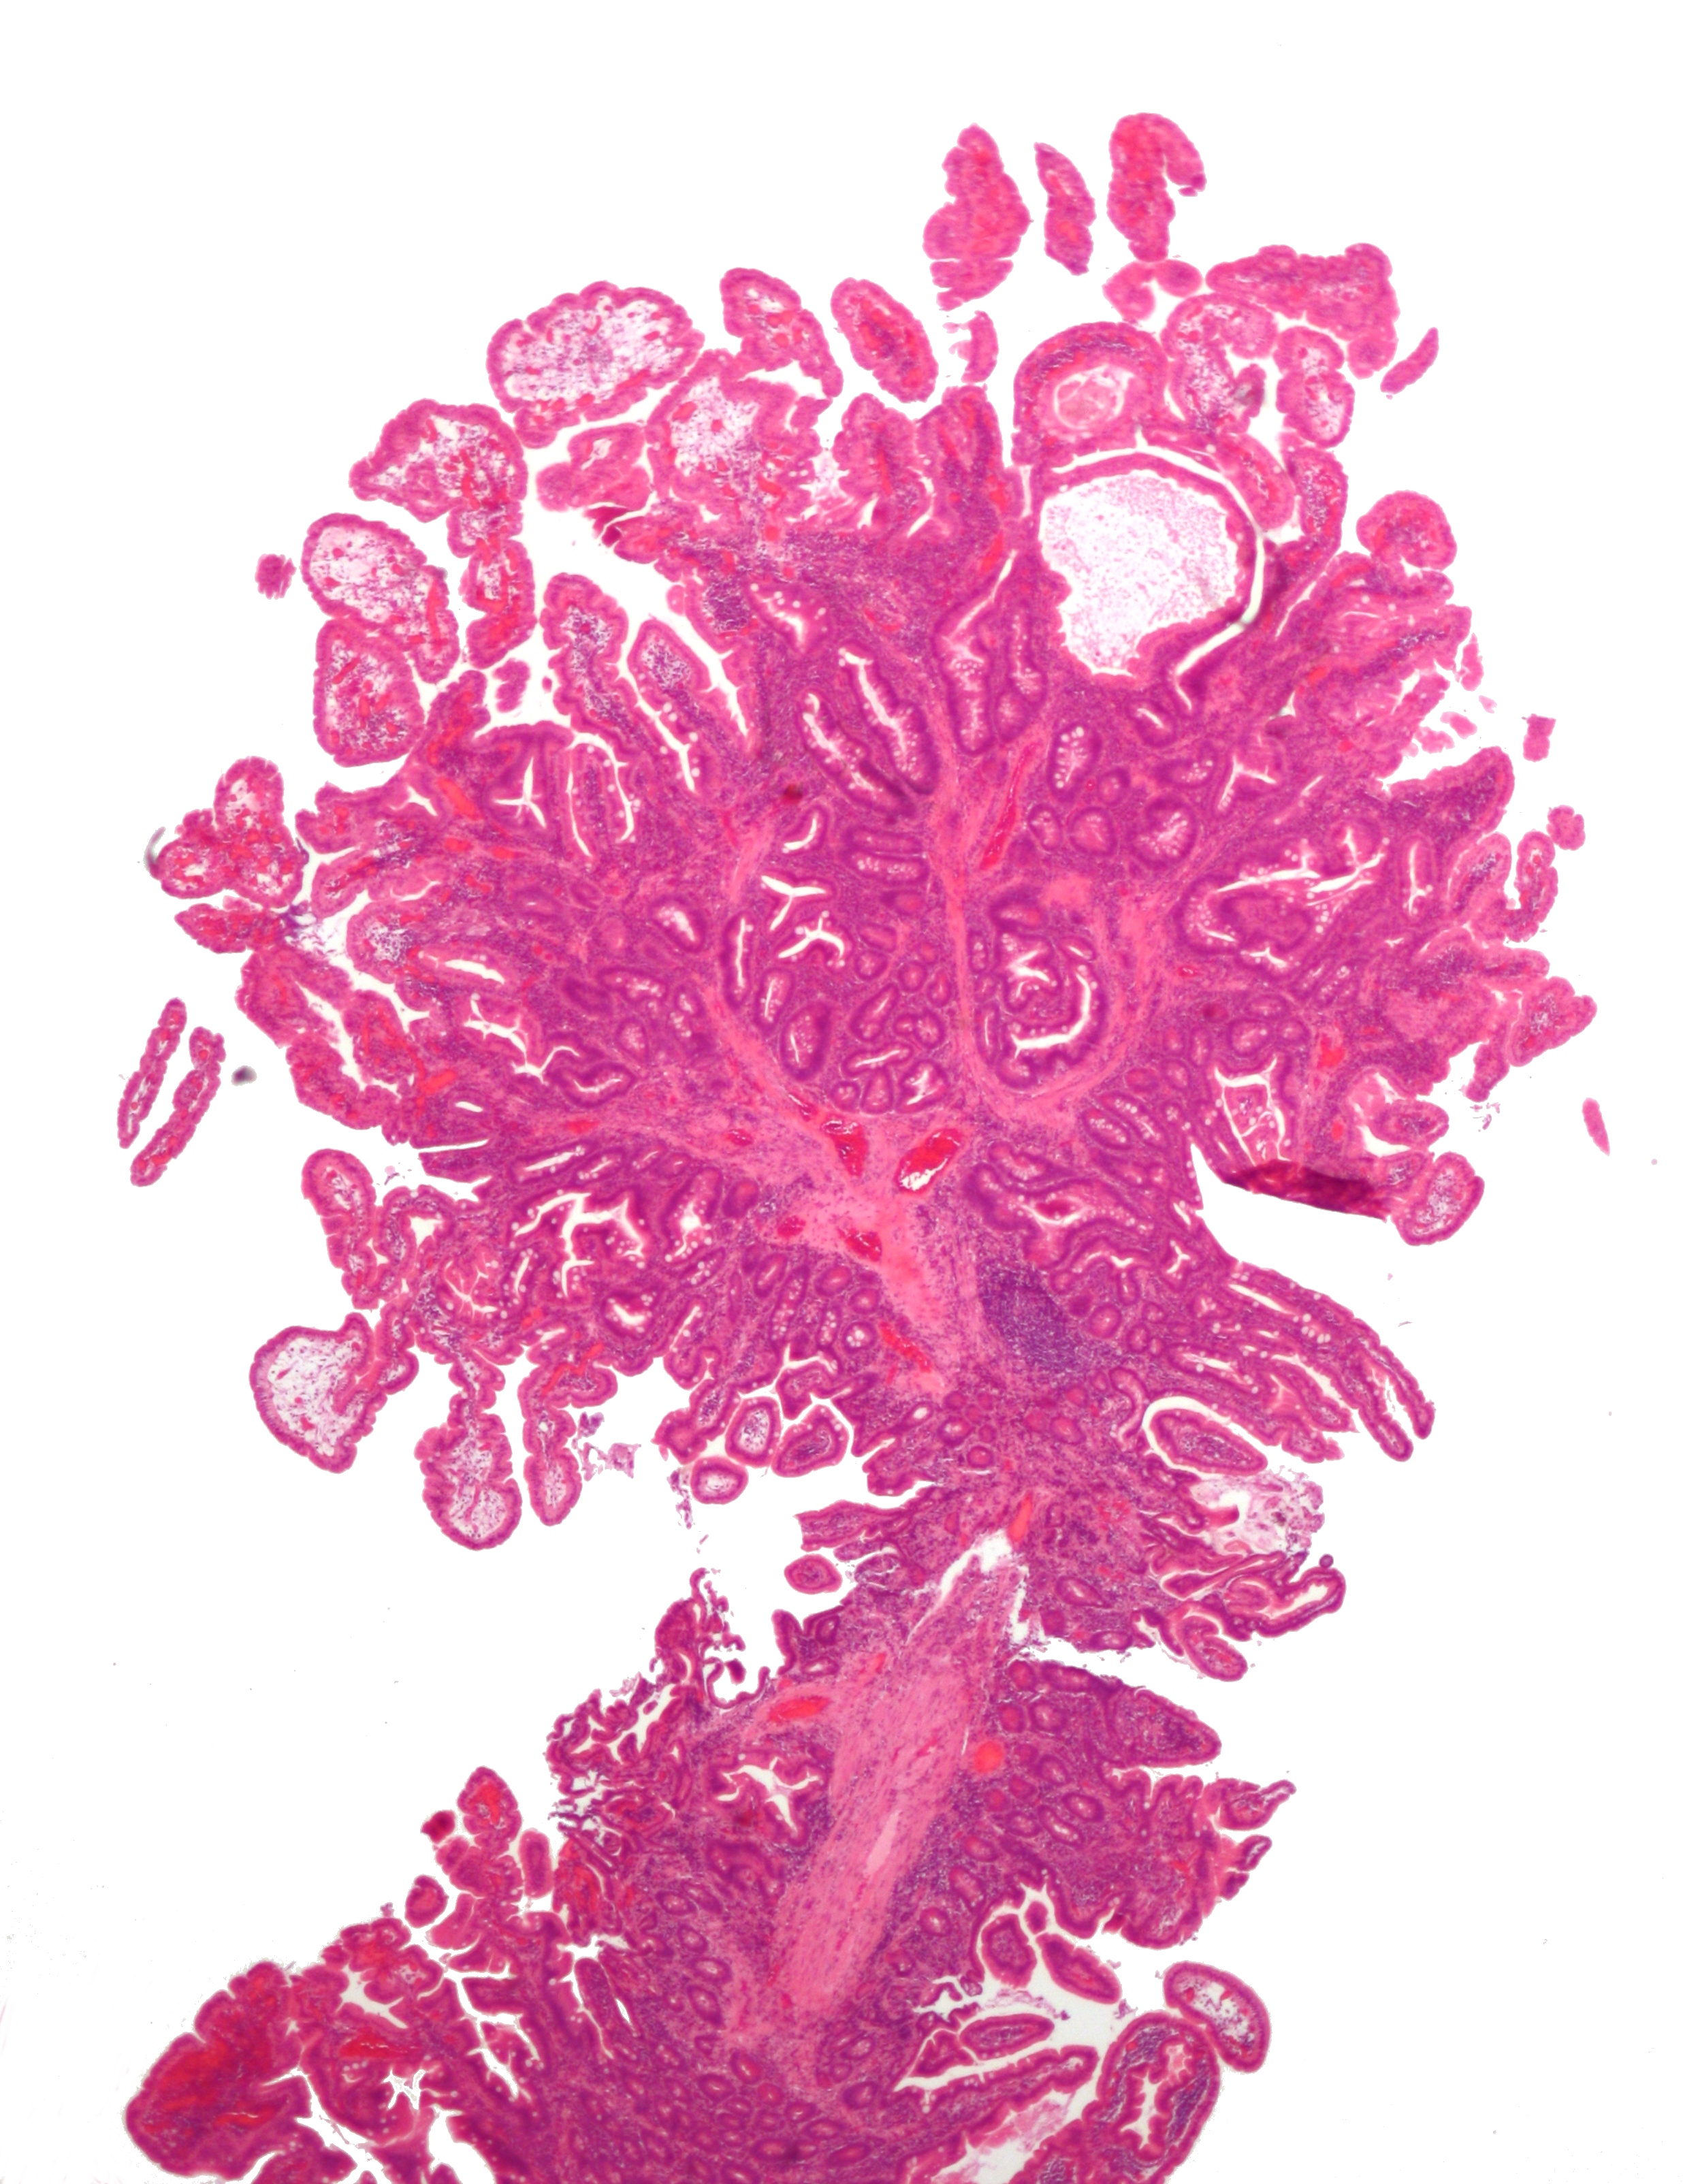

| Peutz-Jeghers 용종 | 모든 소화관 | 비종양성 상피와 "크리스마스 트리" 모양 사이의 평활근 다발 | 아니오 | ![]() | Peutz–Jeghers 증후군 |

| Peutz-Jeghers 용종 | 모든 소화관 | 비종양성 상피와 "크리스마스 트리" 모양 사이의 평활근 다발 | 아니오 | Peutz–Jeghers 증후군 | |